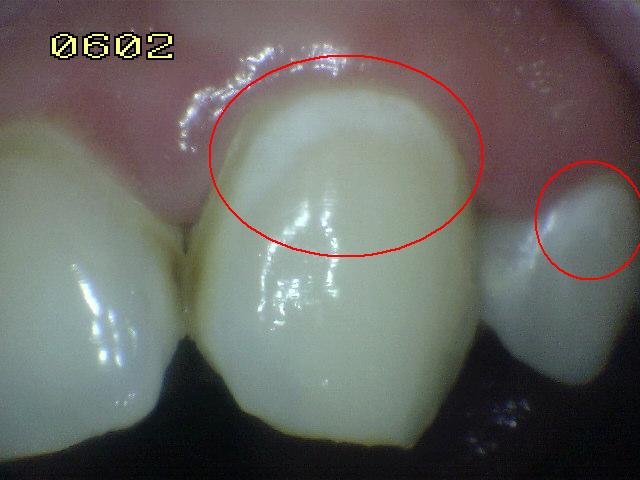

Código 4

(Caries Moderada): Sombra oscura

de dentina

subyacente al esmalte intacto con o sin interrupción localizada del

esmalte

- Esta lesión aparece como una sombra de

decoloración visible a través de una cresta marginal,

aparentemente intacta, o con pequeña micro-cavidad o perdida

de continuidad del esmalte, después del secado con aire por

5 segundos.. Las paredes vestibular o lingual

del esmalte dejan traslucir dentina decolorada.

Este aspecto se ve a menudo con más facilidad cuando el

diente está húmedo. El área oscura es una sombra intrínseca

que puede aparecer como gris, negro-azul o marrón-anaranjado

- Puede utilizarse

una sonda periodontal para identificar

la micro-cavidad en esmalte o discontinuidad < 0,5 mm.